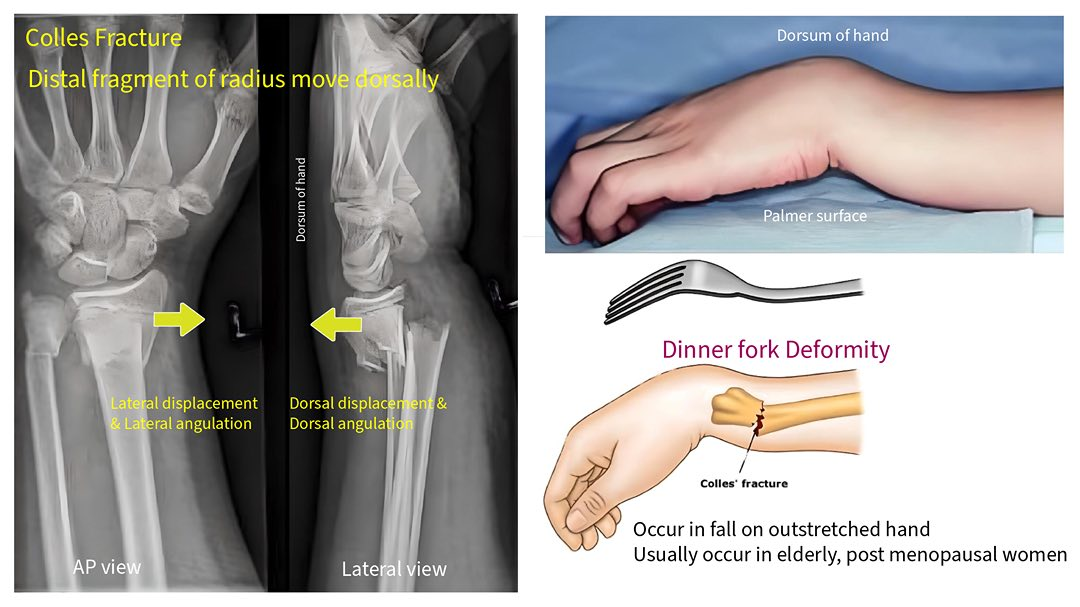

colles fracture

common extra-articular fracture

bone break that does not involve the articular surface (the surface of the bone that forms part of a joint)

occurs as a result of a fall on an outstretched hand

posterior displacement

medial angulation of the distal radius (tilting of the distal fragment of the radius bone toward the ulna)

posteroanterior hand radiograph of a 63-year-old female who fell

colles fracture

Radiolucent, linear (?? i think this is meant to be transverse) fracture of the distal radius, with rotation

rotation evident by superimposition (overlap) of structures

Angulation and displacement cannot be commented on without a lateral view